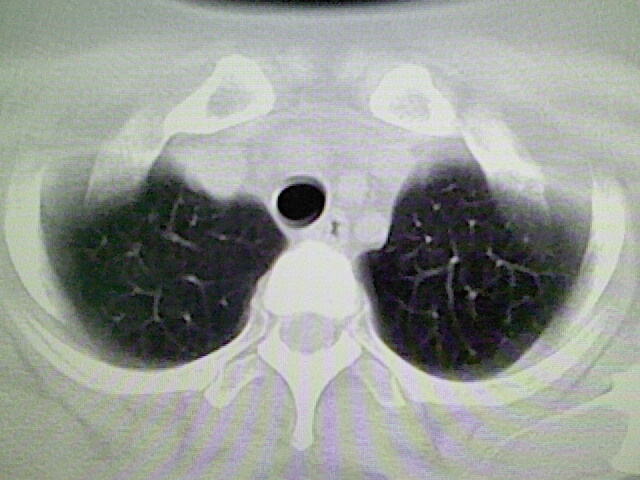

女,52岁,咳嗽,咳痰多日

左下肺陈旧纤维索条!

左肺舌段炎性改变

我见过几例,为炎症后纤维条索

慢性炎症后改变

考虑慢性炎性病灶粘连牵拉改变。

左肺舌叶纤维锁条病变。

左肺上叶下舌段炎症并局部胸膜反应。

左肺舌叶纤维索条影。

左肺舌叶段陈旧性病变

左肺舌段炎性反应。片子的质量太不好了。

左肺舌段炎性

炎性改变

左肺舌叶纤维索条影